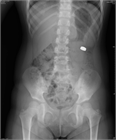

1. CTは、異物の描出のみならず、縦隔気腫、穿孔、腸閉塞など合併する重篤な病態の評価にも有用であり、可能であればCTの施行が望ましい(推奨度2)